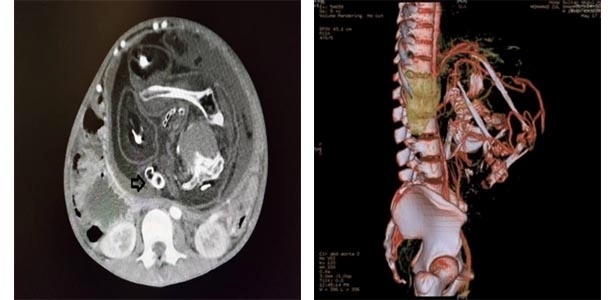

Na imagem à esquerda, tomografia mostra região intra-abdominal de jovem de 15 anos com massa no interior. A flecha indica a coluna vertebral do feto. Na imagem à direita, a massa localizada na região do abdome e da pelvis tem destacados os vasos arteriais que a alimentavam

Exames realizados no hospital revelaram uma enorme massa, medindo 18,5 cm de largura e 23,8 cm de comprimento, se estendendo entre a pelve e a região sub-hepática do adolescente. O feto identificado possuía crânio, coluna vertebral e outros ossos, além de artérias, cabelo, genitália masculina, olhos e pele. Todos esses tecidos possuíam má formação. Ele não possuía boca e não havia cordão umbilical ou placenta.